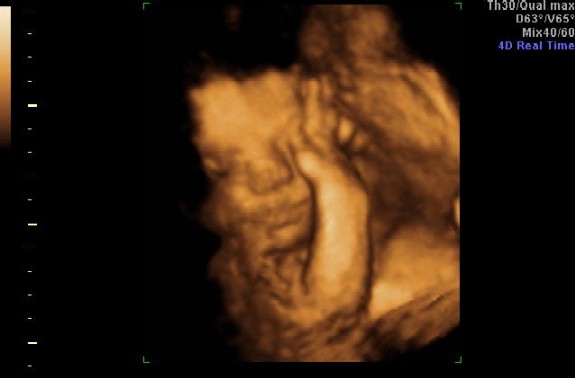

Azt mondta az UH-n a doki, hogy anatómiailag nagyon rendben vannak a babák, de nem túl fotógének és ez igazis. Felteszem a képeket, de nem nagyon látszik semmi.

Ja mindketten fejjel lefelé vannak most épp. Anna 870 g, Zalán 920 g, akkora egyikük mintha csak 1 gyermek lenne a pocimban.

Ja a két felső képen Anna látható az alsókon Zalán.